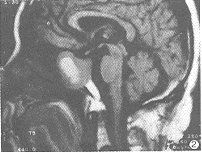

MRI信号特征:9例HPA瘤体在T1WI和T2WI均呈高信号。在T1WI上,6例呈均匀一致的高信号(图1),其余3例呈不均匀的高信号。1例表现散在点状高信号,1例瘤体中心高信号(图2),1例瘤体上半部分高信号,下半部分等信号(图3),。1例EHF引起的垂体出血在T1WI和T2WI呈不均匀的高信号,Gd-DTPA后见血肿轮廓明显强化,肿胀垂体实质略有不均匀强化(图4)。1个月后复查,肿大垂体已明显缩小,大小0.6cm,信号均匀(图5)。

图2 HPA。T1WI矢状位,瘤体中心呈高信号,周围等信号